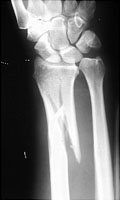

- Click on the image for a larger versionBAP radiograph of the wrist. There is a comminuted fracture of the radius with radioulnar joint dislocation.